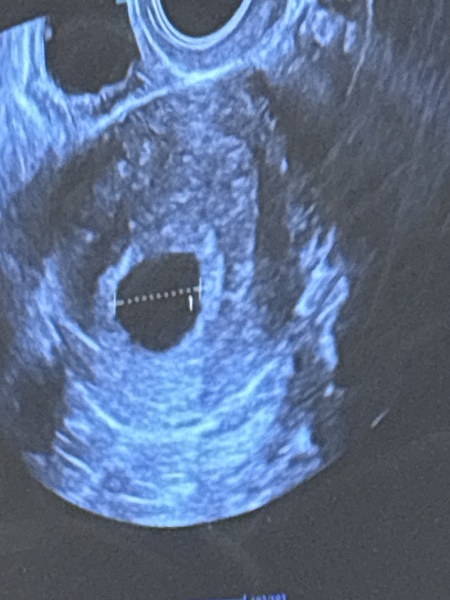

Just to update, no more blood, just some brown discharge and went for a scan today. Measuring exactly 6 weeks 4 days which is bang on for when I ovulated AND saw a beautiful heartbeat fluttering away 💕🥹💕

TMI Photos - Brown discharge 6/7 weeks.

Ahhh congrats OP. What happy news! Congrats 👏 must have been implantation bleeding or a hematoma (which is what they said mine was!) Good luck for the rest of your pregnancy xx

They could see where the bleed had come from on the scan and said it was most likely old implantation bleeding that had made its way out, hopefully I won’t get anymore but they said if I get more brown spotting that’s probably what it is! 🤞💕🙏